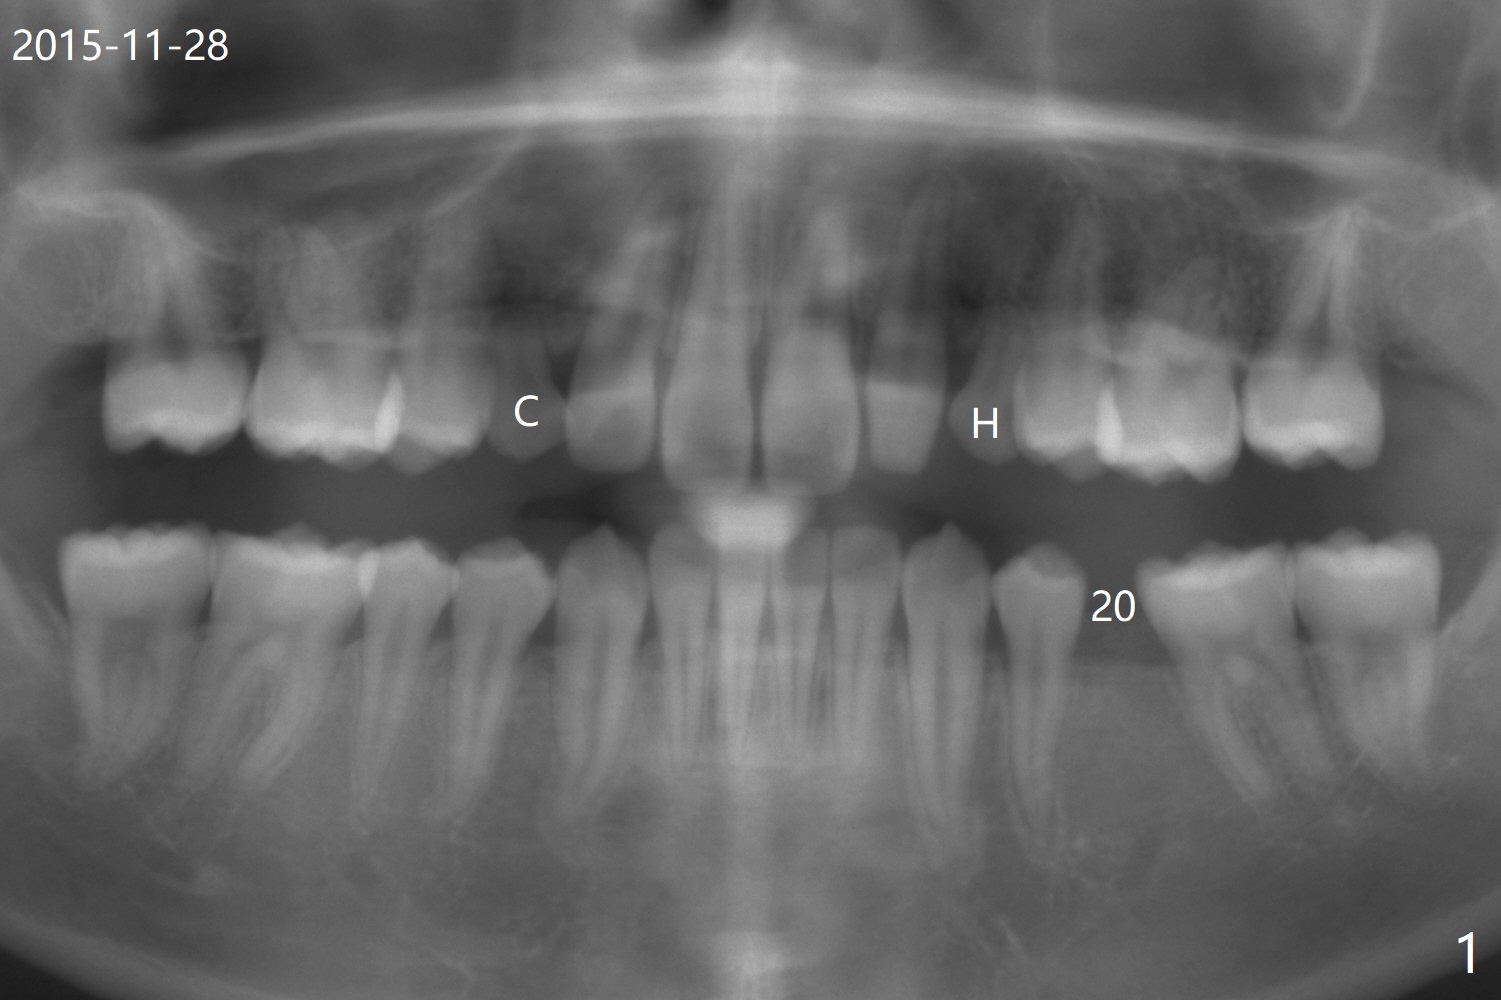

A 20-year-old man requests implant for the loose upper left deciduous canine. Pre-orthodontic panoramus shows 3 implants are needed (Fig.1). Post-ortho PAs indicate root resorption of the upper right deciduous canine as well (Fig.2,3). To reduce radiation, 5x5 cm CBCT is taken for the anterior maxilla, the 1st implant to be placed at #11 in the Thanksgiving this year, while the 2nd one at #6 early next January (Fig.4,5). 1-piece implants may simplify treatment.